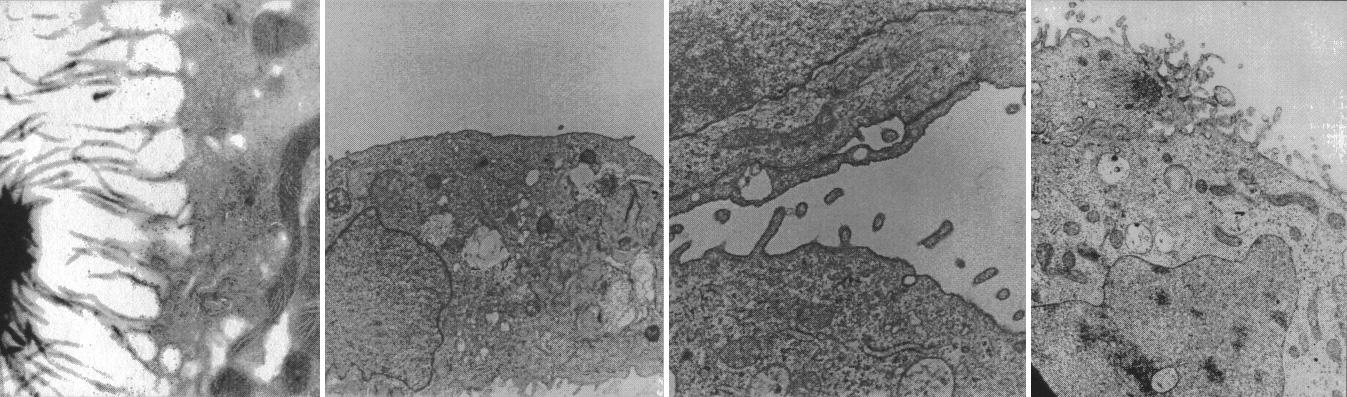

Cells from kidneys lose some of their special features in conventional culture but form spheres replete with specialized cell microvilli (hair) and synthesize hormones that may be clinically useful. Ground-based research studies have demonstrated that both normal and neoplastic cells and tissues recreate many of the characteristics in the NASA bioreactor that they display in vivo. Proximal kidney tubule cells that normally have rich apically oriented microvilli with intercellular clefts in the kidney do not form any of these structures in conventional two-dimensional monolayer culture. However, when normal proximal renal tubule cells are cultured in three-dimensions in the bioreactor, both the microvilli and the intercellular clefts form. This is important because, when the morphology is recreated, the function is more likely also to be rejuvenated. The work is sponsored by NASA's Office of Biological and Physical Research. The bioreactor is managed by the Biotechnology Cell Science Program at NASA's Johnson Space Center (JSC).